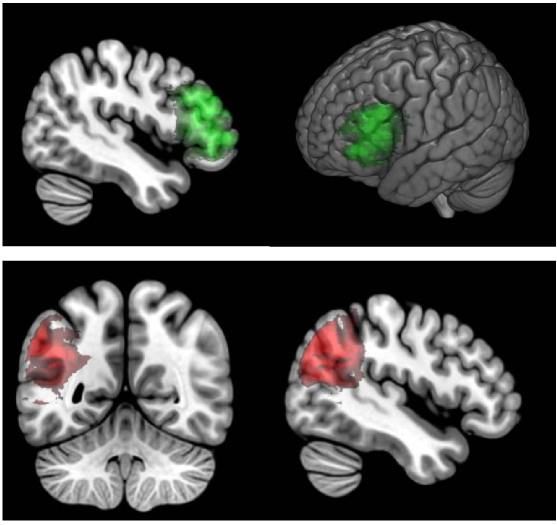

In order to have a deficit score with a known neural correlate, we calculated the percent damage in two brain regions that are widely-studied and frequently damaged in middle cerebral artery stroke aphasia: BA 45 and BA 39 (see Figure 1). An effective statistical correction strategy should approximately identify these areas (i.e., damage in BA 45 is the ``neural correlate" of percent damage in BA 45) and the permuted data will provide additional insight into the method’s ability to reject false positives.

Figure 4 shows the results of permutation-based cluster size correction (at ) for simulated deficit scores of percent damage in BA 45 (top row) and BA 39 (bottom row). It is immediately apparent that the identified region expends beyond the bounds of the true region, covering an area that is perhaps twice the size of the Brodmann Area where percent damage was used as the behavioral score.

For comparison, we used the maximal t-value from the same 1000 permutations to compute permutation-based FWER-corrected thresholds for each of these analyses. The resulting t-thresholds were 5.52 for BA 45 and 5.39 for BA 39 and the thresholded maps are shown in Figure 5. This approach did a reasonably good job of identifying the critical regions.

We explored using a permutation approach for determining a minumum cluster size threshold for statistical correction of VLSM. This approach is adapted from analysis of functional neuroimaging data (Nichols and Holmes,, 2002) and has been previously used in VLSM (Pillay et al.,, 2014; Mirman et al., 2015a, ). Using structural lesion data from 124 participants left hemisphere stroke, we constructed deficit scores using percent damage in BA 45 and BA 39. These behavioral scores were used to assess the permutation-based cluster size correction method on three criteria (1) correctly detecting the relationship between damage to BA 45 or BA 39 and the corresponding deficit score, (2) falsely detecting clusters in the permutations (which, by definition, have no lesion-deficit relationships), and (3) incorrectly detecting voxels outside the critical BA 45 and BA 39 regions.

When only the largest cluster was used, the false positive rate was controlled (i.e., 95% of all permutations had no clusters that passed the cluster size threshold) and the critical BA regions were correctly identified. However, the supra-threshold clusters extended well beyond the boundaries of the correct BA regions. This pattern suggests that permutation-based cluster size correction can correctly reject no-signal cases but is insufficiently spatially specific when a true relationship exists. That is, when there is no consistent lesion-deficit relationship, this method should produce false positive clusters at the rate specified by the permutation threshold: at cluster threshold , there is less than 5% chance of detecting a cluster if no lesion-symptom relationship exits. However, if a lesion-symptom relationship does exist, this method will detect the correct region but spatially contiguous regions will also be included in the critical cluster. This spill-over effect may lead to incorrect interpretation of the results, so a better method is needed.